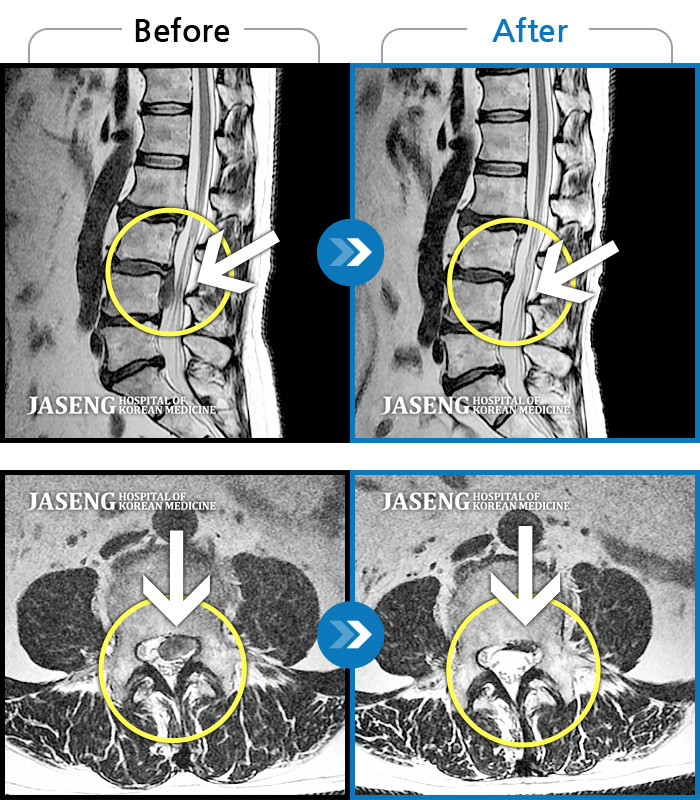

Before

After

환자에게 사전 동의를 받아 동일 조건에서 촬영되었습니다.

개인에 따라 치료 후 부작용이 발생할 수 있으니 의료진과 상담 후 치료를 진행하시기 바랍니다.

허리디스크로 인한 허리통증

좌측 허리 통증 및 좌측 허벅지, 정강이의 통증과 저림, 감각근력저하